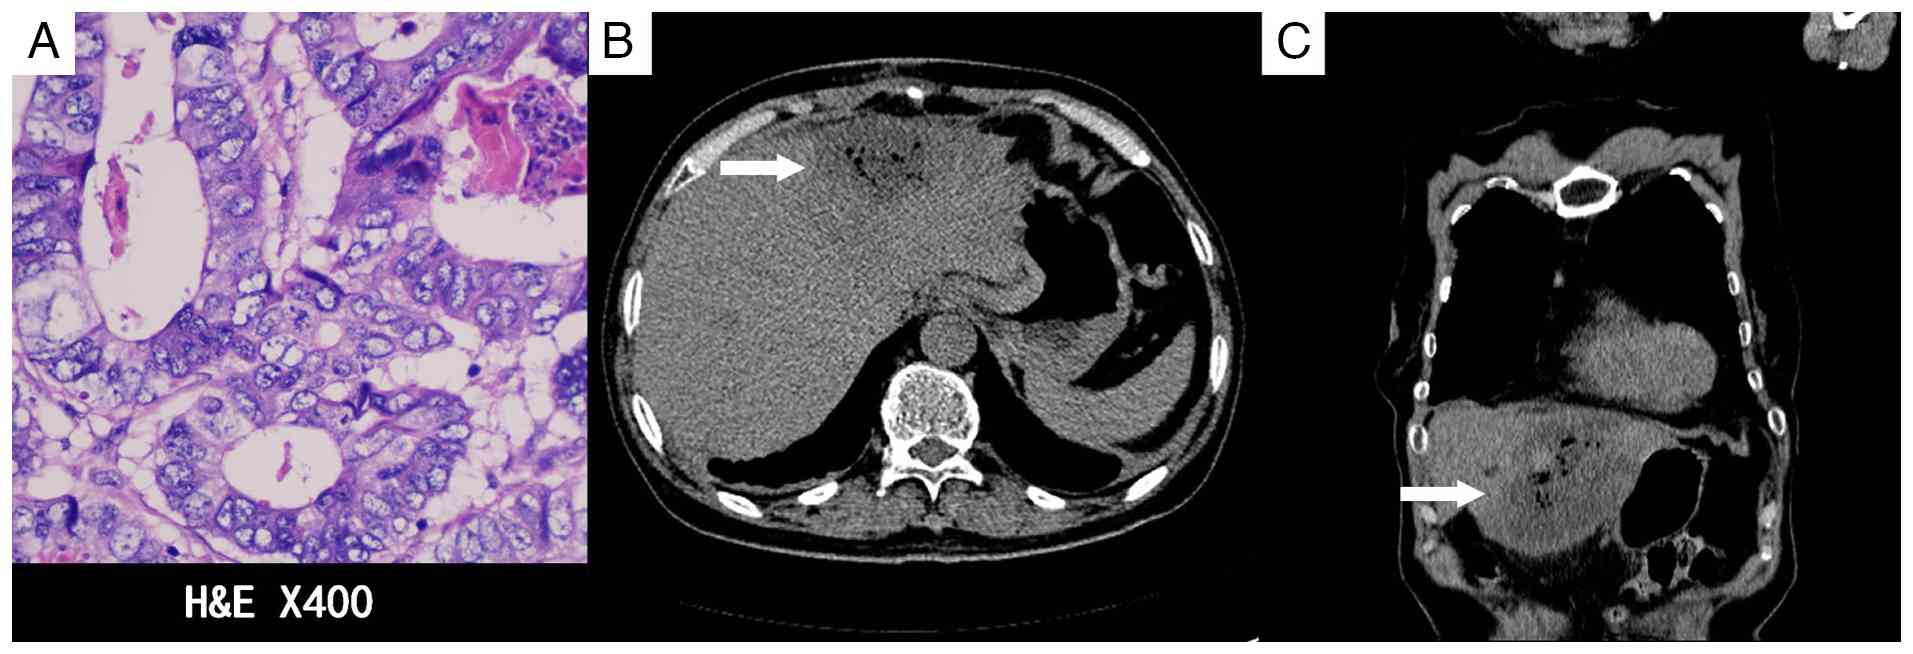

A total of 5 days after the initial chemotherapy treatment, the patient was admitted to the in the Department of Hepatobiliary Surgery and underwent RFA with a concurrent biopsy of the left hepatic lobe lesion. The postoperative pathology, performed as aforementioned, confirmed liver metastasis of colorectal cancer. The cells were arranged in irregular glandular structures with infiltrative growth, and the nuclei were enlarged, with prominent nucleoli (Fig. 3A). The patient developed abdominal pain and a fever following the operation. A CT scan 1 week after RFA revealed signs of infection (Fig. 3B and C), which recovered after antibiotic treatment. In October 2013, the chemotherapy regimen was switched to XELOX (1,500 mg capecitabine orally twice daily on days 1–14; 180 mg oxaliplatin by intravenous infusion on day 1), followed by TACE 8 days later, targeting the metastatic lesions in the right hepatic lobe. A contrast-enhanced CT scan conducted 10 days post-TACE showed no significant reduction in the size of the three lesions in the right hepatic lobe compared with the size in the images taken before the procedure, with persistent mild enhancement (Fig. 4).

Pathological and computed tomography

imaging in the left lobe of the liver following radiofrequency

ablation. (A) Histopathology of the lesion in the left lobe of the

liver reveals that the cells are arranged in irregular glandular

structures with infiltrative growth. The nuclei are enlarged and

nucleoli are prominent. The pathological diagnosis is metastatic

colorectal carcinoma to the liver. (B and C) A clustered

heterogeneous density shadow can be seen in the left lobe of the

liver, with gas density shadows within it (arrow). The adjacent

greater omentum is thickened. The results suggest infection.

Figure 3.

Pathological and computed tomography imaging in the left lobe of the liver following radiofrequency ablation. (A) Histopathology of the lesion in the left lobe of the liver reveals that the cells are arranged in irregular glandular structures with infiltrative growth. The nuclei are enlarged and nucleoli are prominent. The pathological diagnosis is metastatic colorectal carcinoma to the liver. (B and C) A clustered heterogeneous density shadow can be seen in the left lobe of the liver, with gas density shadows within it (arrow). The adjacent greater omentum is thickened. The results suggest infection.